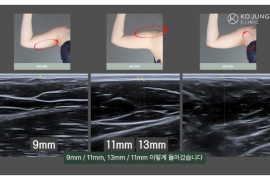

바디·체형